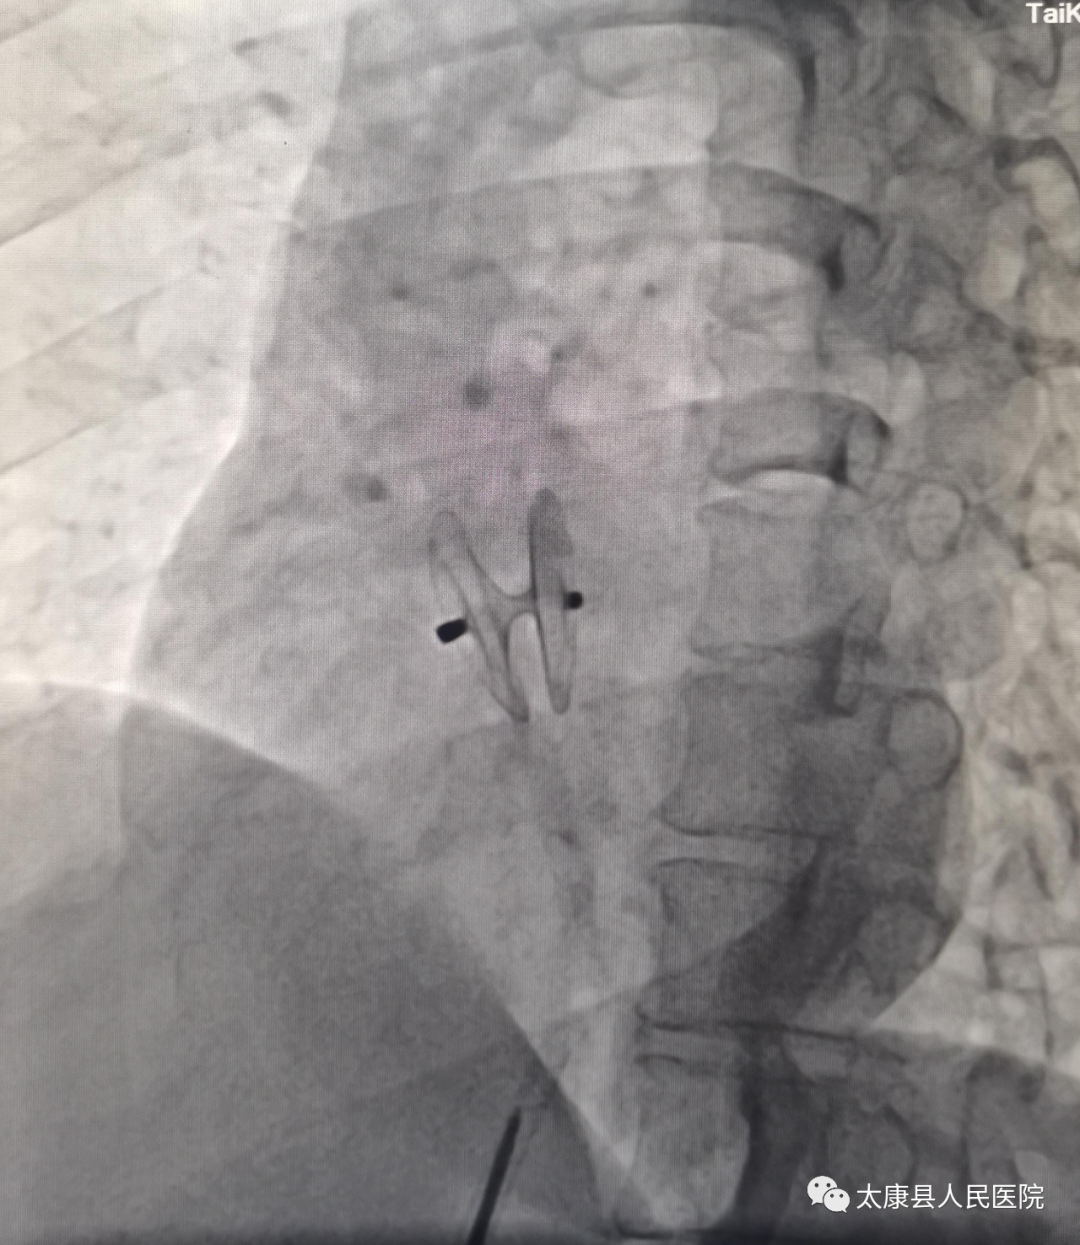

完善术前相关检查后,心血管内科一病区介入团队在阜外华中心血管病医院刘煜昊教授指导下,成功为患者进行了卵圆孔未闭封堵术,手术过程非常顺利,手术时间<30分钟,术后患者头痛症状明显缓解,现已顺利出院。

该患者女性,反复不明原因头痛10余年,入院后在我院超声科高艳灵主任大力支持下,完善右心声学造影检查示:发泡试验阳性(RLS III级),考虑卵圆孔未闭,请张东旭主任医师查房后指示进一步完善经食道超声检查,检查结果示:卵圆孔未闭 。卵圆孔未闭隧道长约12mm ,宽约2.0mm。经我院心内一病区医师团队讨论,并结合阜外华中心血管病医院刘煜昊教授的意见,在与患者及家属充分沟通后,决定为患者进行卵圆孔未闭封堵术治疗。